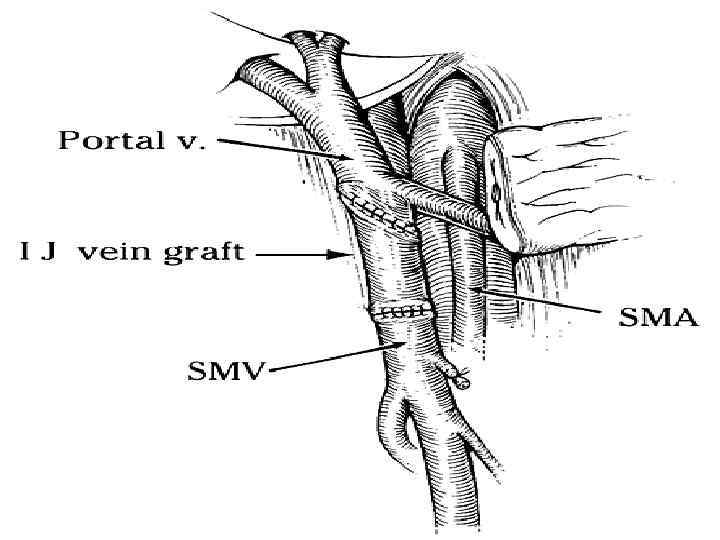

Классификация вовлечения магистральных сосудов по Nakao et al в зависимости ангиографической картины и сравнение с данными послеоперационного гистологического исследования Ангиографические типы Гистологическое подтверждение вовлечения сосудов (%) Тип А – не измененная ангиограмма 0 Тип В – одностороннее сужение 20 Тип С – двухстороннее сужение 70 Тип D – стеноз, обструкция с наличием коллатеральных вен 92